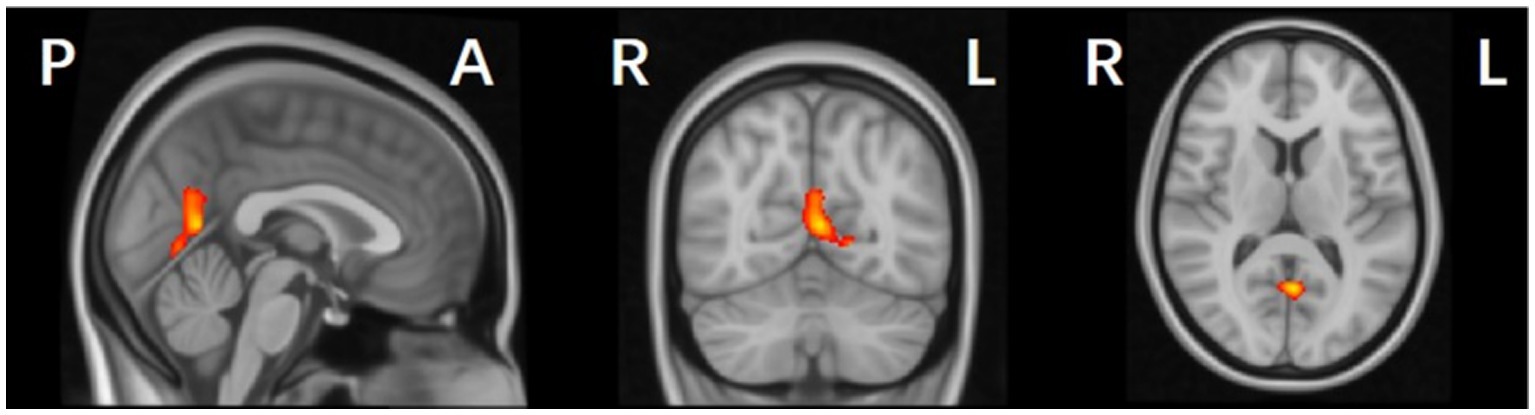

3.3 Group comparisons and correlation analysis of gray matter volume based on VBM

Compared with the HC and PD-NC groups, the PD-MCI group exhibited localized reductions in gray matter volume (GMV) in the left parieto-occipital region, including the calcarine, lingual gyrus, and precuneus (p < 0.05, FWE corrected; Table 3 and Figure 3). No regions with significantly increased GMV were found in the PD-MCI group. There were no statistically significant GMV differences between the PD-NC and HC groups.

Figure 3

Gray matter volume (GMV) reduction regions in PD-MCI compared with HC group (p < 0.05, FWE corrected).

Table 3 and Figure 3 illustrate the cortical regions with GMV reductions in the PD-MCI group. Spearman correlation analysis showed that GMV reductions in the left medial parieto-occipital cortex were positively correlated with MoCA scores (p < 0.001, R = 0.565) (Figure 4), suggesting that structural atrophy in this region may be associated with cognitive decline in early-stage Parkinson’s disease.